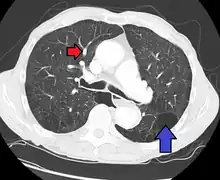

Uma avaliação diagnostica completa inclui uma historia, exame físico, radiografia de tórax, provas de função pulmonar, eletrocardiograma (ECG), ecocardiograma, imageamento de ventilação perfusão e cateterismo cardíaco. Em alguns casos, pode ser necessária uma biopsia pulmonar, realizada por toracoscopia, visando elaborar um diagnóstico definitivo. O cateterismo cardíaco do lado direito do coração revela a pressão arterial pulmonar elevada. Um ecocardiograma pode avaliar a progressão da doença e excluir outras condições com sinais e sintomas similares.

O ECG revela hipertrofia ventricular direita, desvio do eixo para a direita e ondas T altas, em pico, nas derivações inferiores, ondas R anteriores altas e depressão do segmento ST e /ou inversão da onda T anteriormente. A Pa O2 também está deprimida (hipoxemia).

Uma cintilografia da ventilação-perfusão ou angiografia pulmonar. As provas de função pulmonar podem estar normais ou mostrar discreta diminuição na capacidade vital (CV) e na complacência pulmonar, com uma leve diminuição na capacidade de difusão.